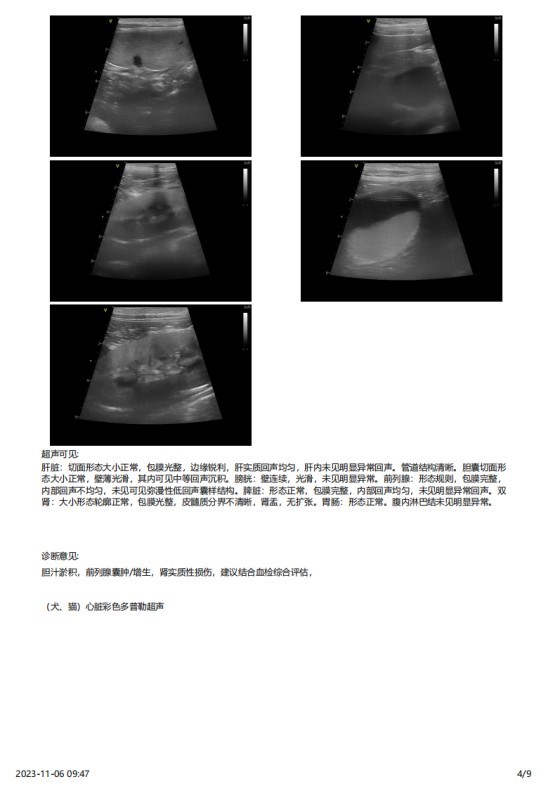

2023 年 3 月份检查结果